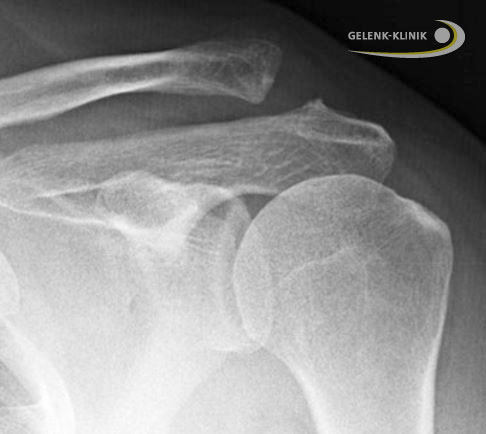

Die Verletzung des Schultereckgelenks wird heutzutage anhand einer Klassifikation nach Rockwood in sechs Stadien eingeteilt. Sie ergänzt die etwas ältere Einteilung nach Tossy, welche ebenfalls eine Aussage über die Schädigung der Bandstrukturen und damit über die Verletzung des AC-Gelenkes gibt.

Die Klassifikation des Schweregrads nimmt der Arzt anhand eines Röntgenbildes unter Belastung vor. Dabei hängt ein Gewicht am betroffenen Arm, das die Fragmente auseinanderzieht. Je weiter die Fragmente in dieser Bildgebung voneinander entfernt sind, desto schwerer ist die Verletzung.

Auch der Zustand der Sehnen und Bänder spielt eine Rolle bei der Einteilung der Schweregrade nach Rockwood bzw. Tossy. Dieser lässt sich im MRT (Magnetresonanztomografie) bzw. Ultraschall (Sonografie) feststellen. An dieser Stelle erfolgt auch die diagnostische Abgrenzung (Differentialdiagnose) zu anderen Schulterverletzungen, die beispielsweise die Rotatorenmanschette betreffen. Bei schwer zu diagnostizierenden Verletzungen kann auch eine Betäubung (Anästhesie) des AC-Gelenks erfolgen. Halten die Schmerzen trotz Betäubung weiter an, ist eine andere Struktur ursächlich für die Beschwerden.